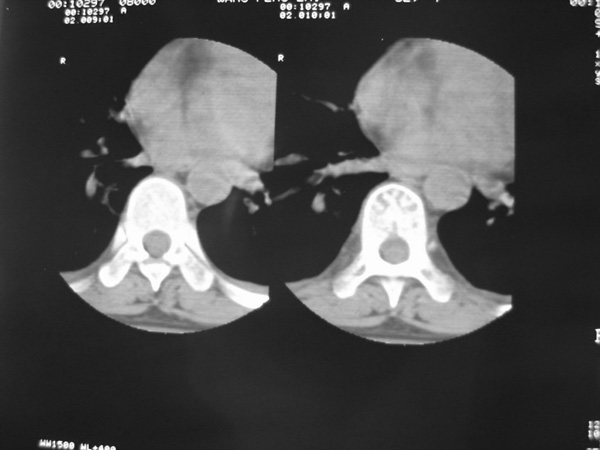

女,45岁,胸背部疼痛2个月。t6、7胸椎病变。

骨窗像结核怎没有了,支持结核。

胸椎体骨质破坏伴死骨形成,椎周环状软组织肿胀,范围较长,考虑胸椎结核伴冷脓肿形成。鉴别;1转移性肿瘤;椎弓根骨质破坏多见,软组织肿块局限。椎间隙尚存。有原发肿瘤病史。2,淋巴瘤;骨质破坏 然骨皮质轮廓线尚存,当椎管骨示环状软组织影时有一定特异性。病变较局限。建议mri增强,观察冷脓肿与软组织肿块很有帮助。